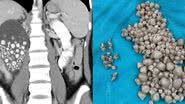

Todas as pedras foram localizadas no rim esquerdo da paciente